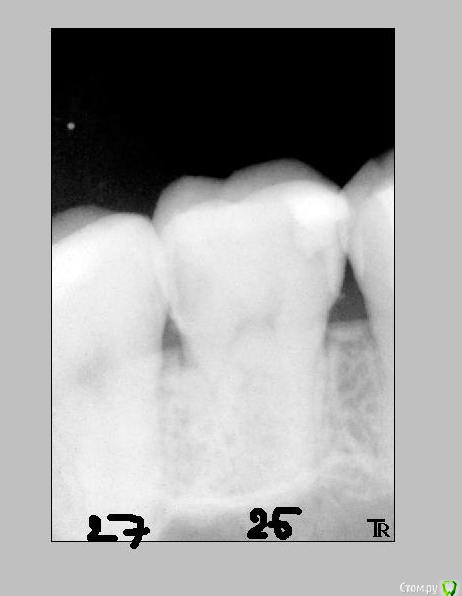

Katya88 Опубликовано 22 декабря, 2014 Поделиться Опубликовано 22 декабря, 2014 Всем здравствуйте. Ситуация такова: заболел зуб справа наверху, болевые ощущения на холодное и горячее, боль при накусывании, к ночи боль усиливалась. У стоматолога сделали снимок, под вопросом были 26 и 27 зуб, снимок этих зубов до лечения №1. В 26 зубе была полость, врач сказал что начнет сверлить, если камера пульповая не вскроется, то удалять ничего не надо, собственно она осталась целой. стоматолога и в 27 кариес, в общем на первом приеме запломбировали оба, стоматолог сказал что если будет ныть то значит в 26 пульпит. Боли не прекратились, а усилились и через неделю мне депульпировали 26 зуб. Сильные боли прекратились, но полностью не исчезли. Через 10 дней боль опять усилилась, и снова появлялась на холодное и горячее, при накусывании и усиливалась к вечеру. Я пошла к стоматологу, путем прикладывания ватки смоченной в горячей воде выяснилось, что болит 27 зуб! И удалили в нем нерв, боли прекратились. Вопросы: мне ошибочно удалили нерв в 26 зубе? Виноват стоматолог? Если пульповая камера целая, то пульпита быть не должно? Как качество запломбированных каналов? Читала что хороший врач на обработку одного канала тратит не менее 30 мин, мой стоматолог три канала обрабатывает за 20 мин))) Мне нужно менять врача? Могло ли быть следующее, сначала пульпит в 26 зубе, а потом в 27? Ссылка на комментарий

CRAZYDUCK Опубликовано 23 декабря, 2014 Поделиться Опубликовано 23 декабря, 2014 По этим снимкам вообще ничего не видно, засвечены сильно , тут контрастность нужно отрегулировать. 1 Ссылка на комментарий

Katya88 Опубликовано 23 декабря, 2014 Автор Поделиться Опубликовано 23 декабря, 2014 По этим снимкам вообще ничего не видно, засвечены сильно , тут контрастность нужно отрегулировать.Вот такие снимки делают в частных стоматологиях, это оригиналы, не сканы и не перфотографированные Ссылка на комментарий

CRAZYDUCK Опубликовано 23 декабря, 2014 Поделиться Опубликовано 23 декабря, 2014 Вот такие снимки делают в частных стоматологиях, это оригиналы, не сканы и не перфотографированныену контрастность на компе врач регулирует и все хорошо видно, а эти снимки скопировали Вам сильно засвеченными почему-то.Пульпит мог быть и в двух сразу зубах, могло так совпасть конечно же. Сделайте еще снимки , потому , что по таким невозможно ничего понять.Пульпит может быть , к сожалению, и в невскрытой полости. Ссылка на комментарий